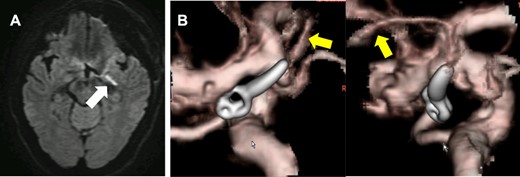

A 59-year-old woman was admitted to our hospital with a history of surgical clipping of an unruptured AchA aneurysm 9 years ago. The aneurysm was incompletely obliterated because of perforating branches arising from the aneurysm dome. A computer tomography (CT) angiogram revealed regrowth of the aneurysm to size with a maximum dome diameter of 6.6 mm (Fig. 1). Neurological examination at admission showed no neurological deficit.

Preoperative CT angiography showed recurrent left ICA–AchA aneurysm and a surgical clip of the previous operation (open white arrow). The yellow arrow points to the AchA main trunk originating from ICA. The white and gray arrows indicate the anterior cerebral artery and ICA, respectively.